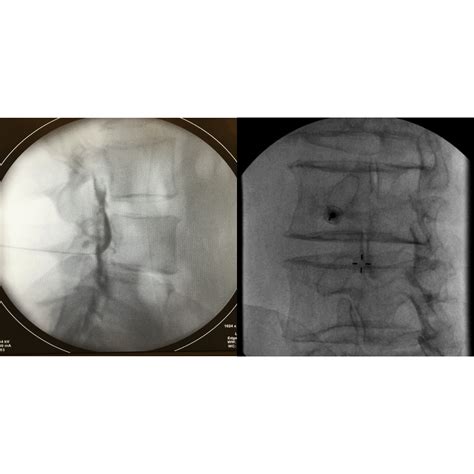

The procedure is typically performed in an outpatient setting, often using fluoroscopic guidance. Fluoroscopy is a form of real-time X-ray that allows the physician to see exactly where the needle is placed, ensuring accuracy and safety.

3. Using fluoroscopic guidance, the physician carefully inserts a thin needle into the epidural space.

4. A small amount of contrast dye is often injected to confirm the needle placement before the medication is administered.